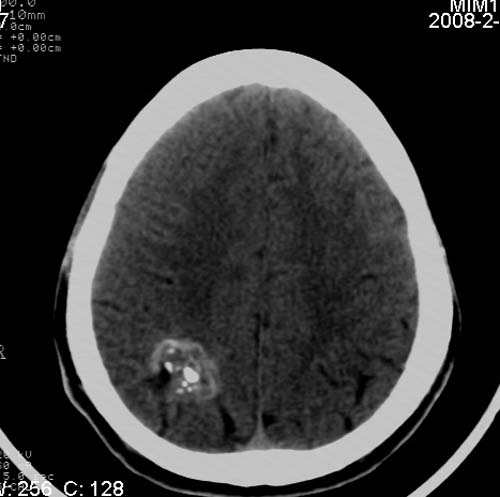

男,17岁,3天前与人斗殴,自述头痛、头晕。无恶心、呕吐,无阳性体征,一般情况良好。

病灶以钙化为主,无明显占位效应,病灶周围无水肿,这种情况应该是脑血管畸形,最多见的是动静脉畸形,其次是海绵状血管瘤.

病人较年轻,有头疼、头晕症状,动静脉畸形可能性大。